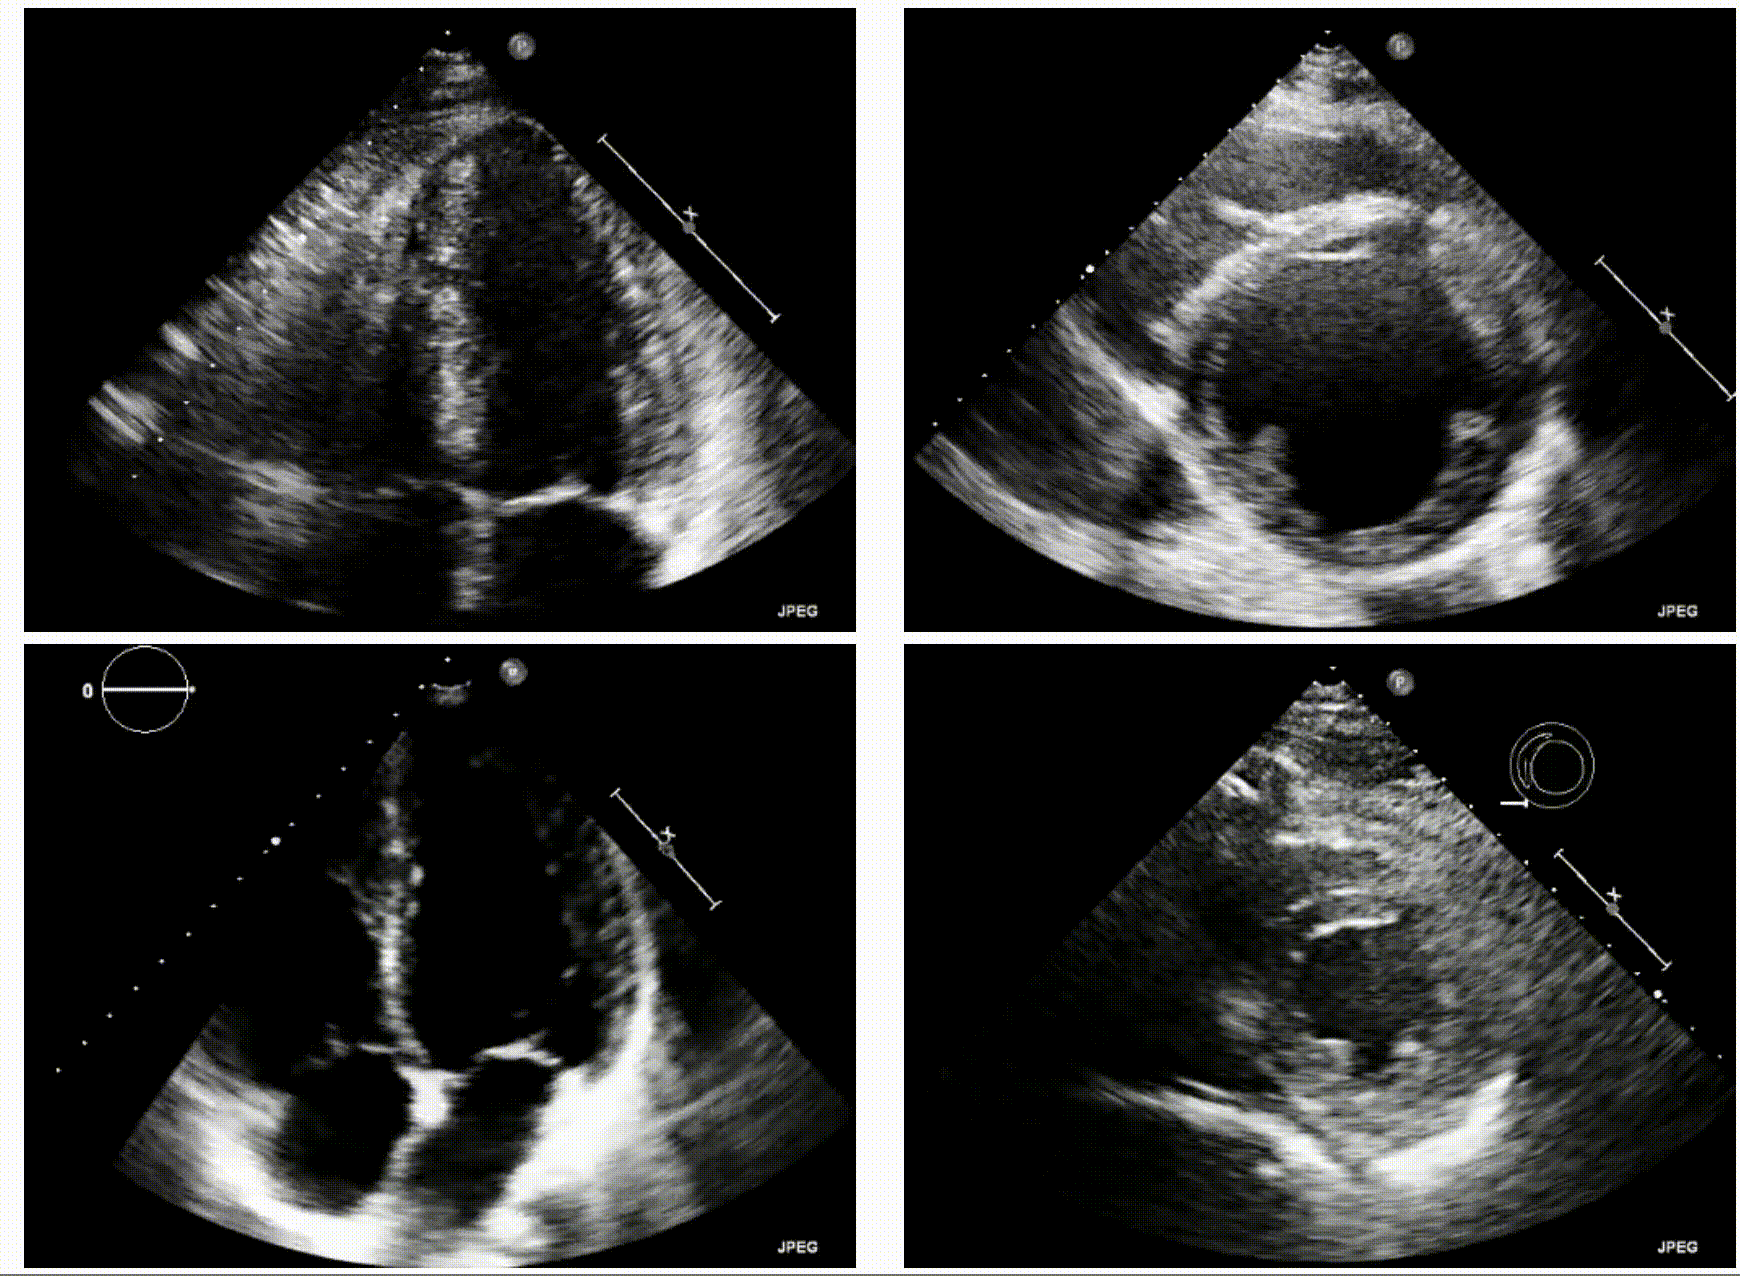

Generation of Synthetic Echocardiograms Using Video Diffusion Models

Alexandre Olive Pellicer, Amit Kumar Singh Yadav, Kratika Bhagtani, Ziyue Xiang, Zygmunt Pizlo, Irmina Gradus-Pizlo, Edward J. Delp

IEEE SSIAI, 2024

project page / paper

• Developed a Video Diffusion Model for generating synthetic video echocardiograms (IEEE SSIAI)